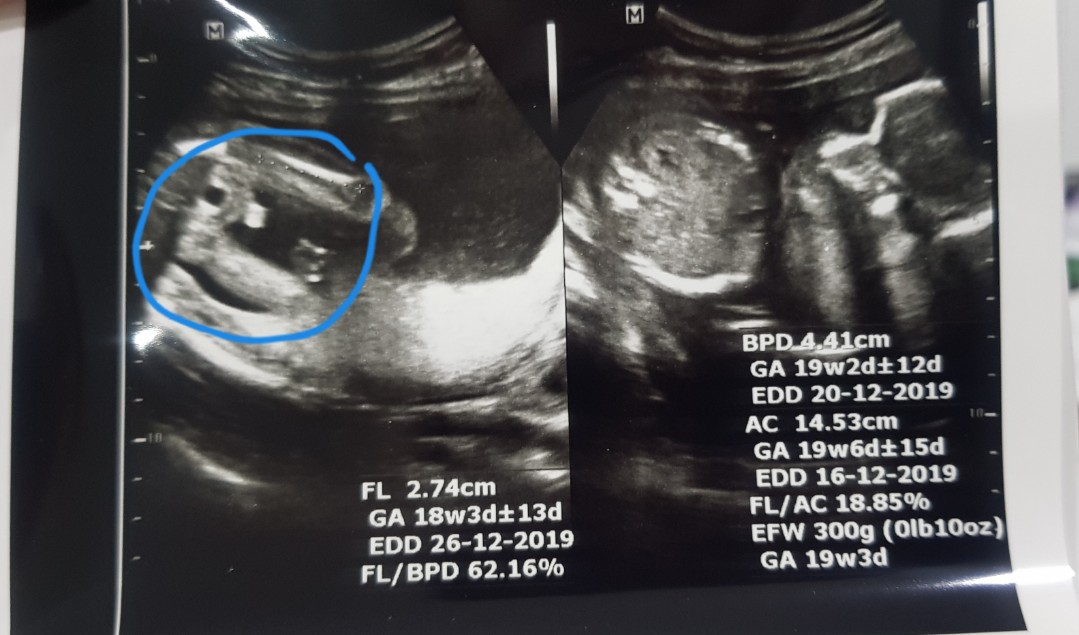

ซาว์ดทั้ง2รอบคุณหมอบอกได้ลูกสาวค่ะ. แม่แอบดีใจมากๆ. คลอดเดือนธันวาคม. แม่ๆบ้านไหนกำหนดคลอดเดือนธันวาบ้างค่ะ ได้ลูกเพศอะไรกัน

กำหนดคลอด 26/12/62 ค่ะ ผู้หญิงจ้า